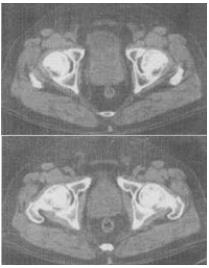

- 单项选择题 男,65岁,尿频尿急及排尿困难,CT检查如图,下列说法错误的是()。

A、前列腺形态呈类圆形

B、前列腺包膜光滑,境界清晰

C、前列腺与膀胱分界清楚

D、考虑为前列腺增生

E、考虑为前列腺癌

- D